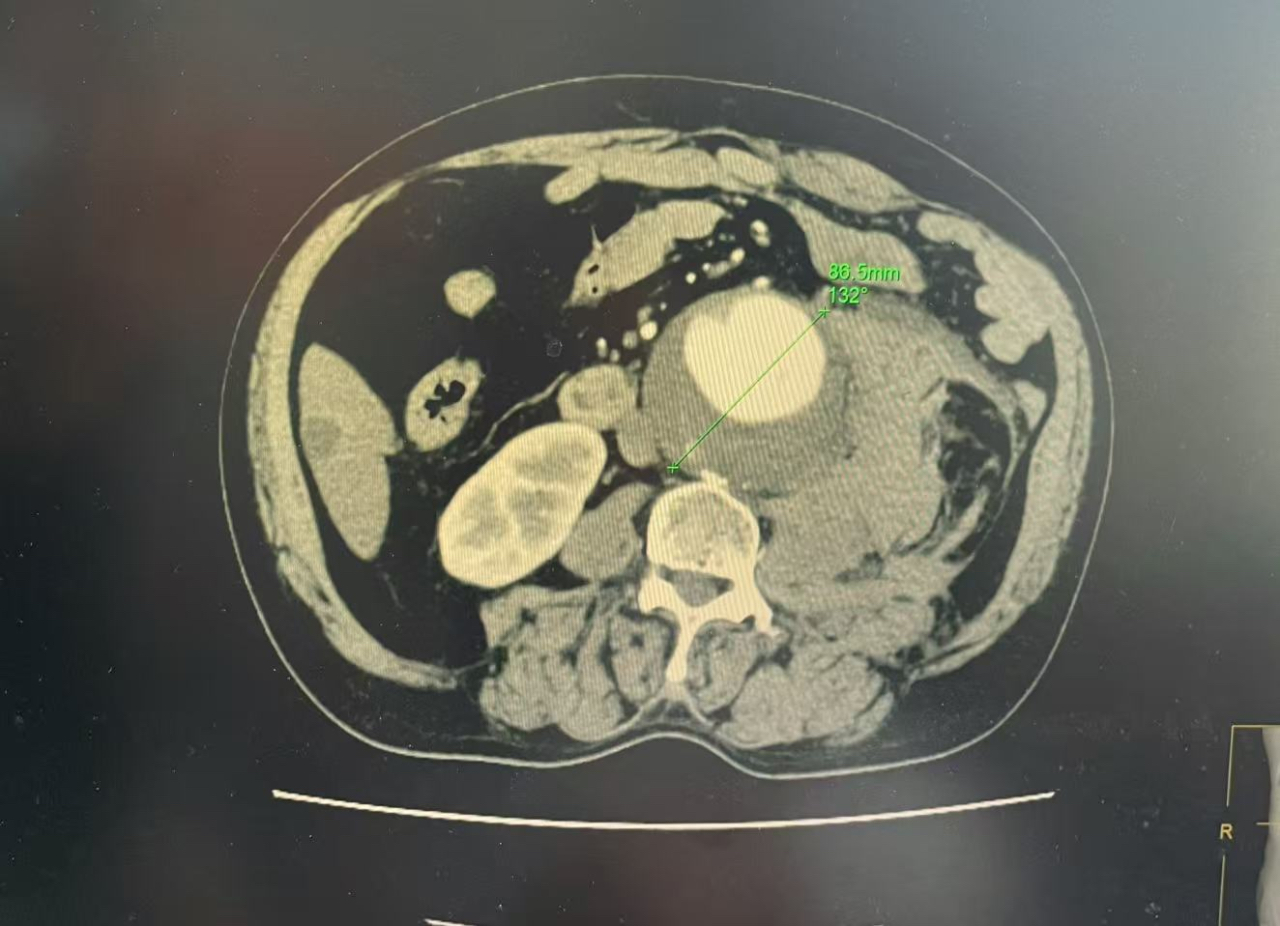

急诊腹部CT检查结果让人揪心:王师傅的主动脉血管直径达到了9cm左右,像“气球”一样被吹大了4-5倍。“正常人血管直径约2cm,差不多手指头粗,而他的血管已经有一个拳头大小。”介入与血管外科主任郝国强博士介绍。而更惊险的是,几年来与患者“和平共处”的腹主动脉瘤也“爆破”了,失血量保守估计达到了1500ml以上,约人体血量的1/3。“患者病情凶险,随时有生命危险,即使手术也面临50%的死亡率。”郝国强介绍。

患者血管直径